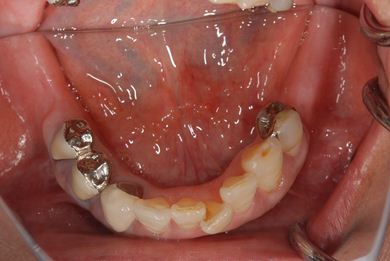

治療前

• 治療前